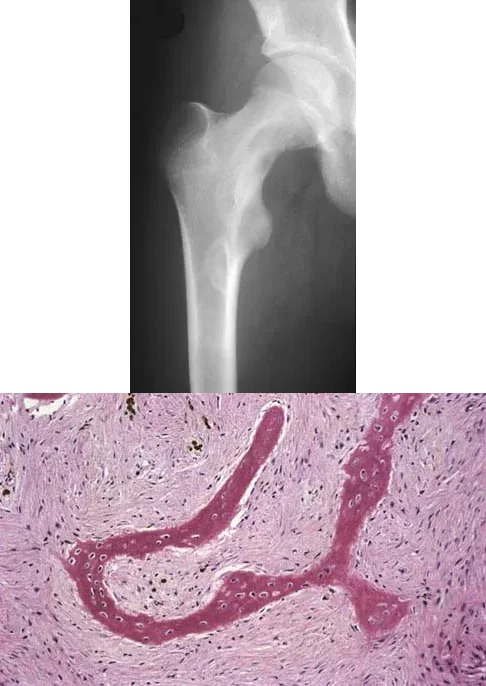

A 13-year-old girl presents with right groin pain and the imaging and histology shown. The histology reveals irregular, woven bone trabeculae in a fibrous stroma without osteoblastic rimming ('Chinese letter' pattern). This condition is associated with a somatic activating mutation in which of the following genes?

Explanation

Correct Answer: B

The clinical, radiographic (ground-glass appearance, Shepherd's crook deformity), and histologic ('Chinese letter' woven bone lacking osteoblastic rimming in a fibrous stroma) findings are diagnostic of fibrous dysplasia. Fibrous dysplasia is caused by a somatic, post-zygotic activating mutation in the GNAS1 gene, which encodes the alpha subunit of the stimulatory G protein (Gs-alpha), leading to increased intracellular cAMP and abnormal osteoblast differentiation.

A 13-year-old girl presents with right groin pain. Radiographs reveal a ground-glass lesion in the proximal femur with a mild 'Shepherd's crook' deformity. Histologic examination demonstrates proliferating fibroblasts in a loose spindle cell background with dysplastic metaplastic trabeculae arranged in a 'Chinese letter' pattern. Which of the following is the most likely diagnosis?

Correct Answer: Fibrous dysplasia

The clinical, radiographic, and histologic findings are classic for fibrous dysplasia. Radiographically, it presents as a lytic, expansile lesion with a 'ground-glass' matrix, often leading to bowing deformities in the proximal femur known as a 'Shepherd's crook' deformity. Histologically, it is characterized by a fibrous stroma containing irregular, woven bone trabeculae that lack osteoblastic rimming, often described as having a 'Chinese letter' or 'alphabet soup' appearance.

A 23-year-old man presents with right posterolateral knee pain, worse at night and relieved by NSAIDs. Imaging and histology are shown. The histologic specimen demonstrates a cellular, vascular stroma with plump osteoblasts producing immature woven bone. What is the currently preferred minimally invasive treatment for this lesion?

The clinical presentation, imaging (cortically based lytic lesion with surrounding sclerosis/edema), and histology (vascular stroma with osteoblasts and woven bone) are classic for an osteoid osteoma. Percutaneous radiofrequency ablation (RFA), typically under CT guidance, has become the preferred treatment method, offering high success rates with minimal morbidity compared to open surgical excision.